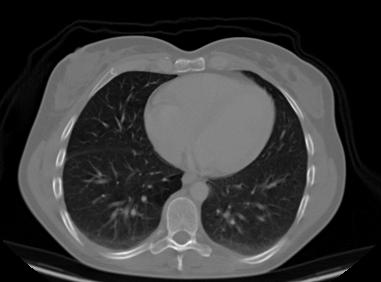

Upload your own CT slice, or click any patient below to instantly see the model classify a real scan.

Try a real scan— click any patient to run inference instantly

INPUT

OUTPUT